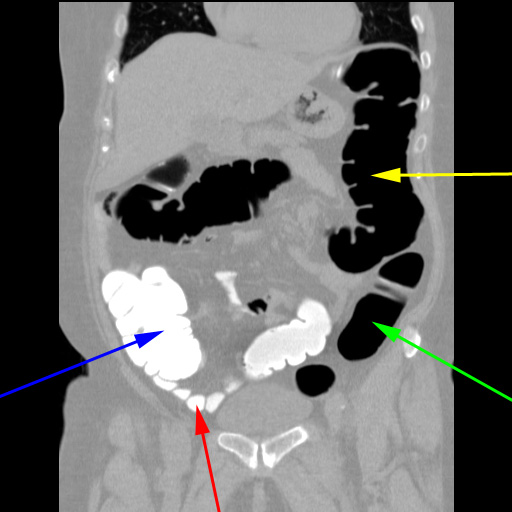

CT-kolografi. Koronal rekonstruktion af de mange tværsnitsbilleder der blev taget, mens patienten lå på ryggen. Man ser, at coecum (blå pil) og terminale ileum (rød pil) er kontrastfyldte, men colon sigmodium (grøn pil) og colon descendens (gul pil) er luftfyldte.